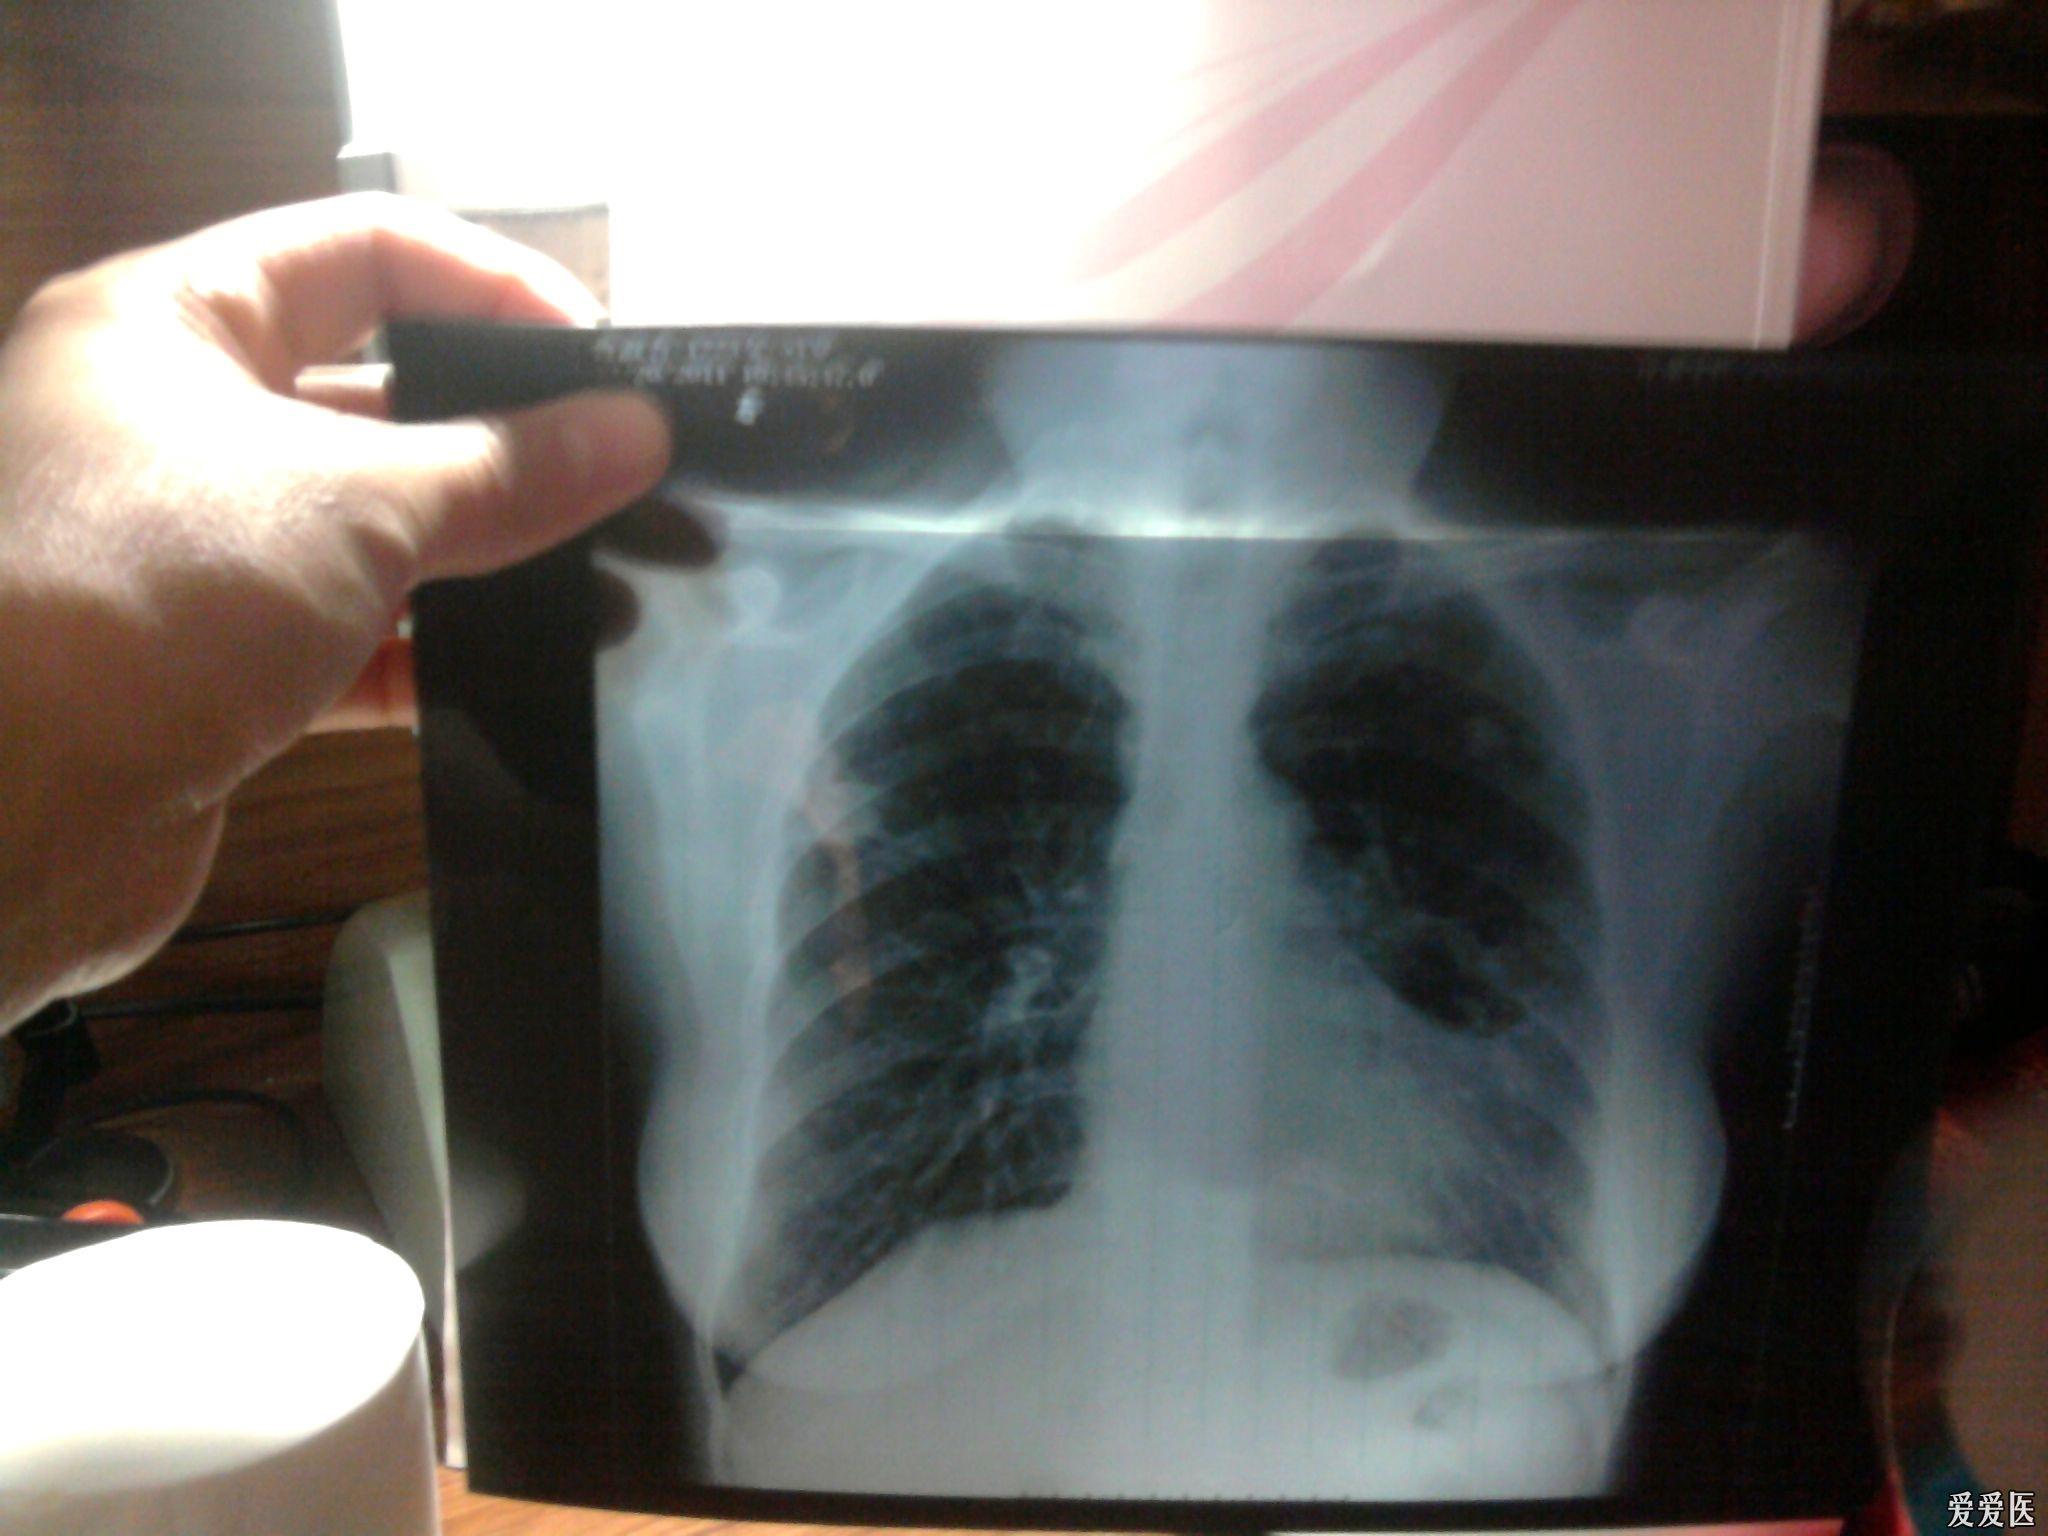

四年前得过肺结核,后治愈,要参加公务员体检了,帮忙看下这张胸片有没

图片尺寸600x800